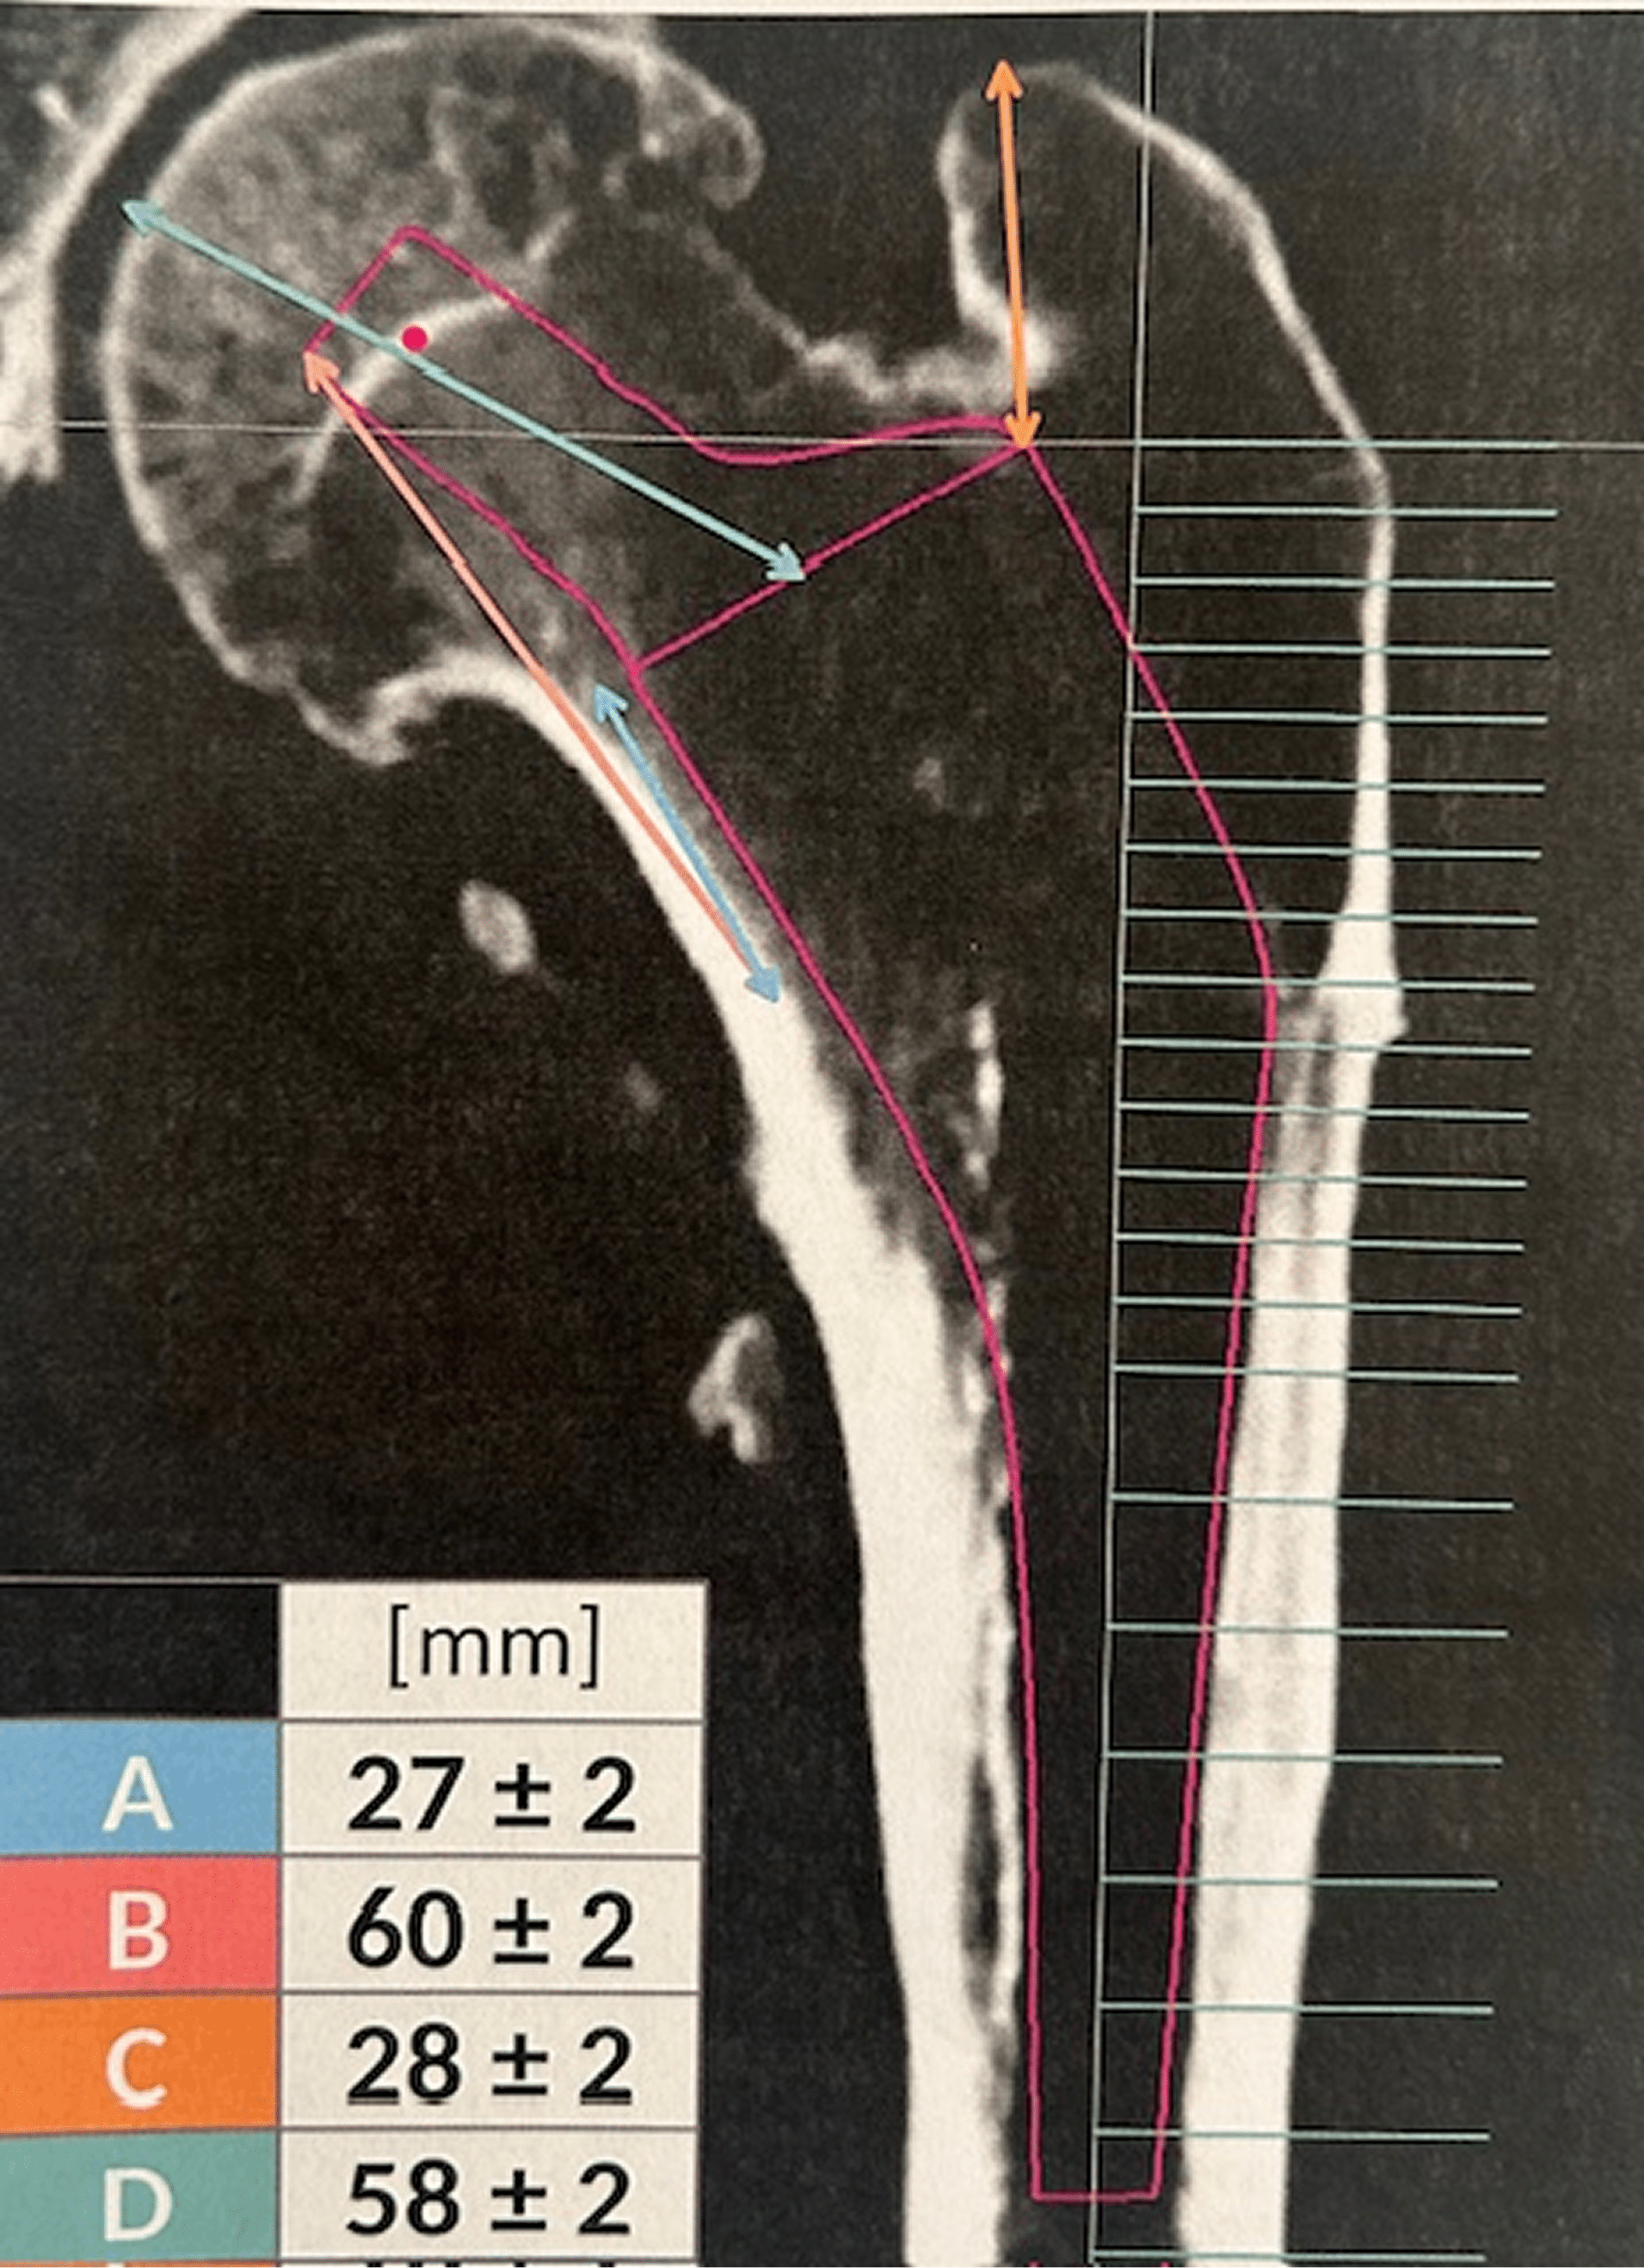

Dr. Londers licht toe: “De misvorming van heup en bovenbeen maakte de ingreep technisch uitdagend. Dankzij een driedimensionale analyse konden we exact bepalen hoe het gewricht moest worden gereconstrueerd en hoe de prothesesteel uiteindelijk diende te passen in het bovenbeen. Zo kozen we voor een volledig op maat gemaakte prothese die het best aansloot bij zijn unieke anatomie.”

De operatie werd minutieus gepland. Zowel de proefprothese waarmee het bot voorbereid werd als het uiteindelijke implantaat werden vooraf op maat gemaakt. Die voorbereiding zorgde ervoor dat de ingreep nauwkeurig en vlot verliep. Ondanks de littekenvorming van eerdere operaties kon via een minimaal invasieve, spiersparende benadering gewerkt worden.

Het traject toont hoe ver orthopedie vandaag staat. Dankzij 3D-technologie kunnen artsen niet alleen visualiseren, maar ook echt op maat werken. In de meeste gevallen volstaat een klassieke prothese perfect, maar bij complexe afwijkingen – zoals bij Kristof – maakt een op maat ontworpen implantaat het verschil.